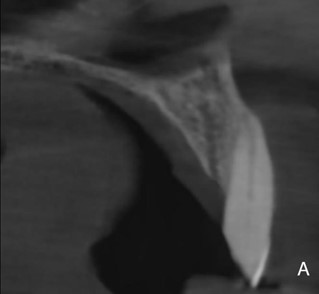

Затем мы оценили 149 визуализированных КС по их расположению в альвеолярном отростке. Установлено, что 76% КС имели нёбную локализацию, а у 12% – как центральную, так и вестибулярную (рис. 4, а, б, в). Эти данные представлены в таблице 3.

Рисунок 4. Визуализация КС в зависимости от локализации: а – небная локализация; б – центральная и в – щечная локализация.